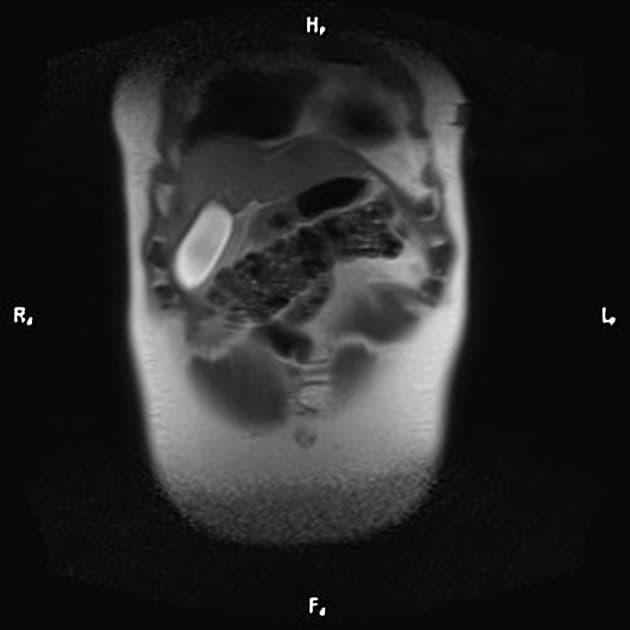

Đã biết hội chứng Von Hippel-Lindau (VHL). Đang sàng lọc các khối u thận. Bệnh nhân có bàng quang thần kinh. Chụp cộng hưởng từ (MRI) được thực hiện nhằm giảm phơi nhiễm tia phóng xạ.

- Nhiều nang thận đơn thuần cũng như nhiều u thận tổn thương hỗn hợp đặc - nang.

- Tuyến tụy cũng chứa một số lượng rất lớn các nang rải rác khắp nơi.

Ca lâm sàng này biểu hiện đầy đủ các đặc điểm của hội chứng Von Hippel-Lindau (VHL), bao gồm nhiều nang thận đơn thuần và nhiều u thận tổn thương hỗn hợp đặc - nang. Tuyến tụy cũng có rất nhiều nang lan tỏa.

Bệnh nhân đã từng được phẫu thuật cắt bỏ u mạch thần kinh đệm (hemangioblastoma) ở tủy sống, gây ra tình trạng bàng quang thần kinh (lưu ý hình ảnh cắt lớp ngang T2 cho thấy dấu hiệu của phẫu thuật cắt mảnh cung (laminectomy) vùng ngực và các thay đổi tại tủy sống).